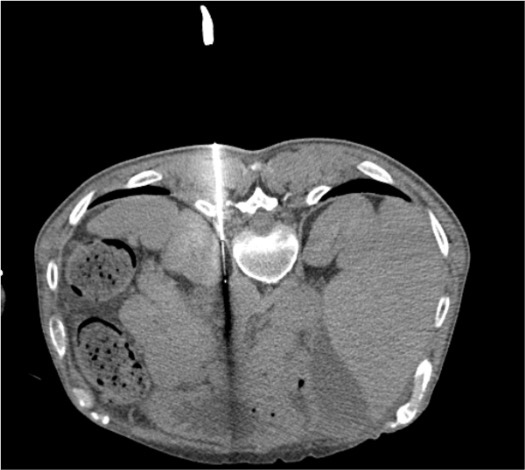

CT Appearance of Celiac Ganglia

The celiac ganglia appear as discoid or lobulated soft tissue structures on axial CT, often resembling the limbs of the adjacent adrenal gland or diaphragmatic crus. The right ganglion is located just posterior to the angle formed by the left renal vein entering the IVC. Bulky retroperitoneal adenopathy from malignancy can obscure the plexus and alter needle access — in such cases, cryoneurolysis may be preferred over chemical neurolysis, as ice ball distribution is more predictable than fluid spread through nodal disease.